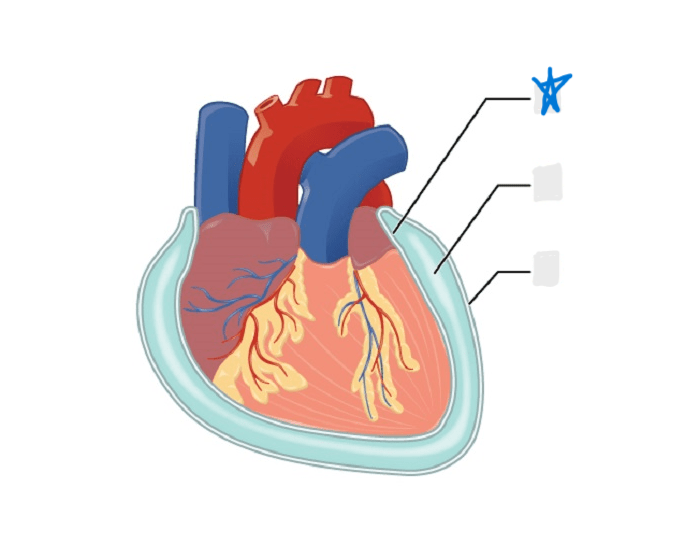

visceral pericardium

parietal pericardium

pericardial cavity